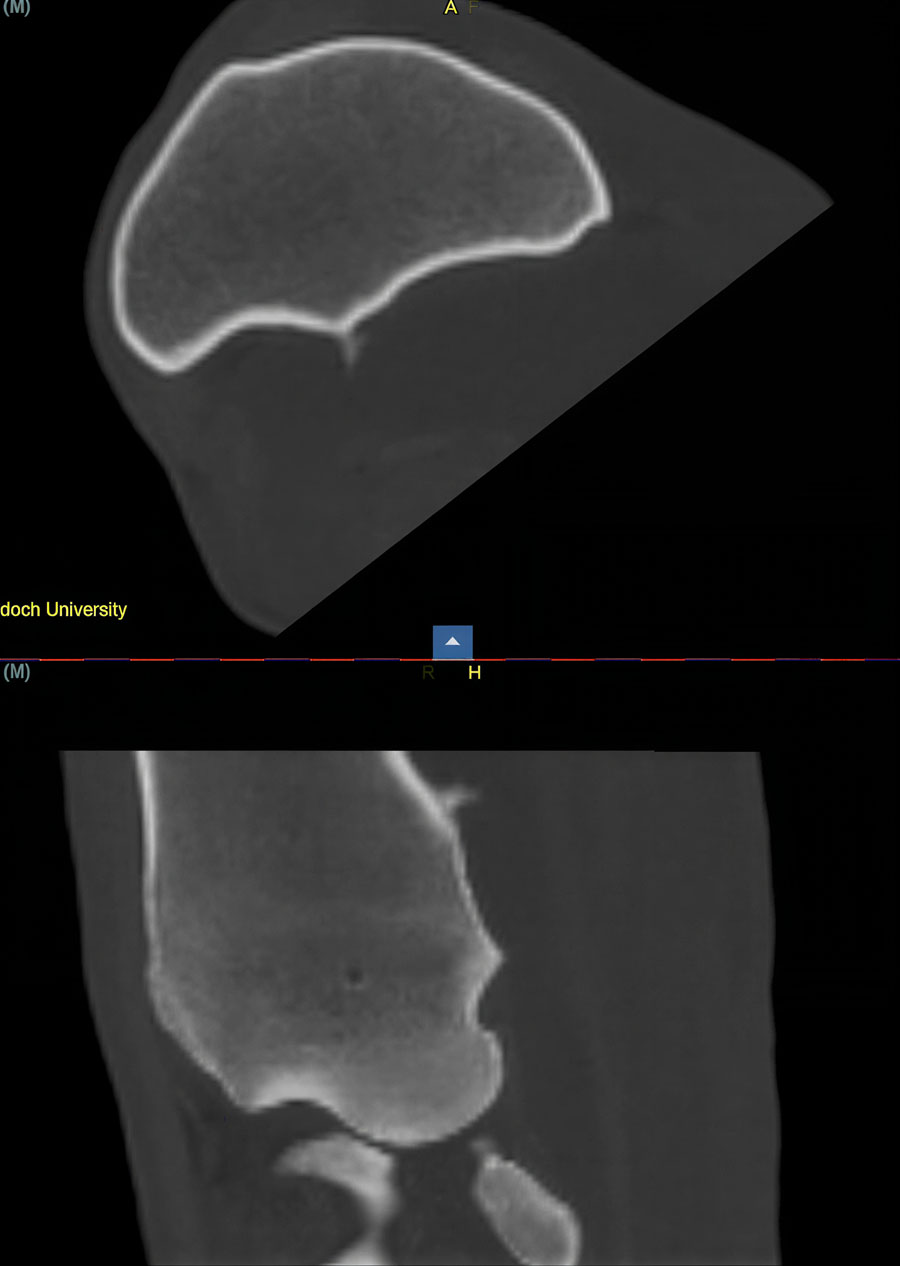

Computed tomography (CT) provides the greatest diagnostic accuracy. CT reconstruction clearly demonstrates the position of the spike, the presence of synovial effusion, and any associated tendon damage. Flexed, non‑weightbearing images may allow tears in the epitenon to open when not under tension, while seeing the spike protruding into the body of the DDFT on a weightbearing image is diagnostic. When available, CT with intra‑thecal contrast is ideal, particularly for surgical planning.

In many cases, CT also helps clarify the extent of tendon involvement, especially when conventional imaging has been inconclusive.

Damage to the DDFT may also be apparent, particularly with flexed, non-weightbearing images allowing tears in the epitenon to open when not under tension. Seeing the spike protruding into the body of the DDFT on a weightbearing image is diagnostic.

If available, CT of the carpal sheath, ideally with intra-thecal contrast, will provide the most accurate diagnostic information, helping guide surgical planning as well as predicting prognosis in the presence of concurrent injury to the region.

A recent case involved a 3‑year‑old Thoroughbred gelding with acute lameness and carpal sheath swelling, having successfully completed multiple races. Radiographs identified a large osteochondroma, and ultrasound confirmed marked disruption to the DDFT. Standard tenoscopic surgery was completed as above, identifying the osteochondroma extending deep into the DDFT. Removal was confirmed using radiography intra-operatively after debridement of the tendon lesion.